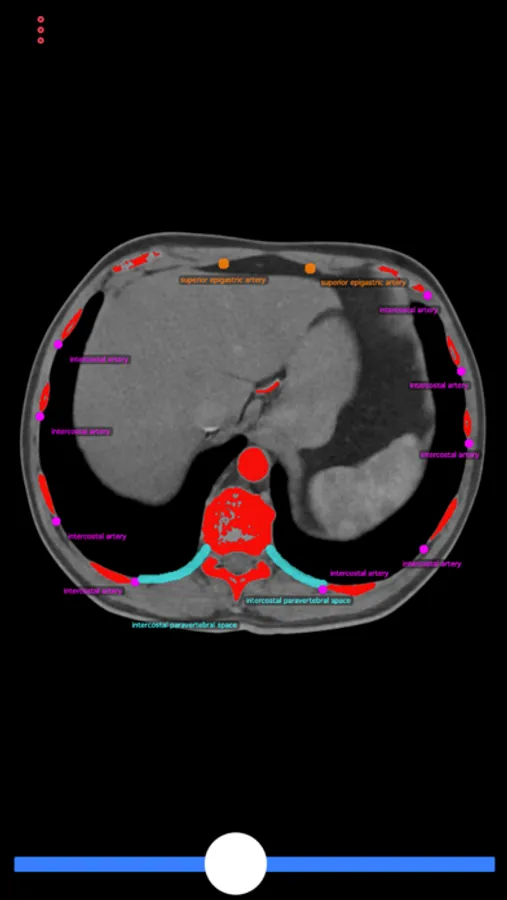

This app consists of body-CT scan (computer-tomography), which demonstrates possible puncture sides and anatomical structures to avoid during the interventions. The user can scroll through the cross sections of the CT scan to find the ideal puncture access.

This app can guide interventional and general radiologists, but also general practitioners or any diagnostic doctor to perform a safe biopsy or drainage catheter placement without injuring the patients.

Biopsy Guide Screenshots

Screenshot 1Screenshot 2Screenshot 3